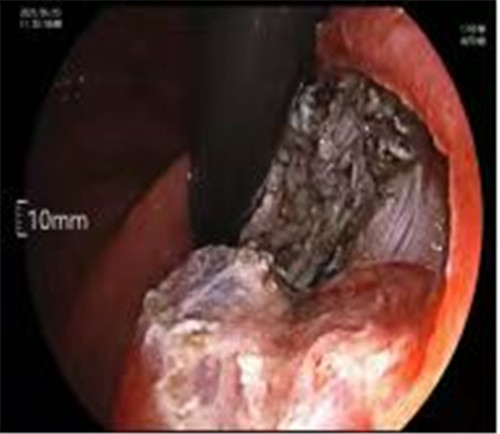

近期病例之一,圖片依次為:胃鏡、超聲胃鏡、ESE術(shù)中、術(shù)后、切下病變。

通過內(nèi)鏡切開瘤體表面粘膜,分離后挖除瘤體,或以消化道全層切除的方法切除瘤體,并在內(nèi)鏡下縫合切口。與傳統(tǒng)手術(shù)相比,該項技術(shù)利用了人體自然通道,不會破壞人體結(jié)構(gòu),更加微創(chuàng)。不超過3cm向消化道腔內(nèi)生長為主的良性或低度惡性粘膜下腫瘤(如間質(zhì)瘤、類癌、平滑肌瘤等),都可采用ESE治療。